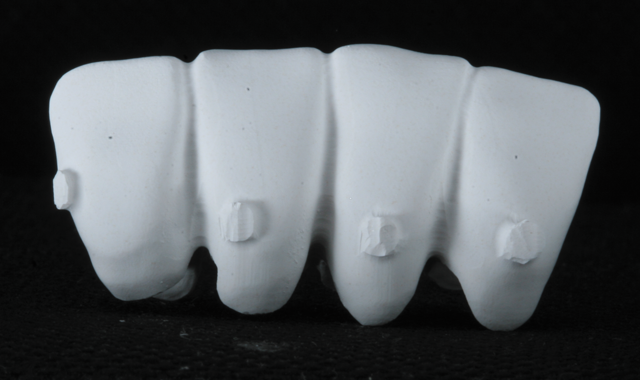

The diagnostic design, as approved by the patient, was then used to create dry-milled provisionals from PMMA using the Zenotec select Hybrid (Fig. 6).

Fig. 6

Additionally, a pattern was created for the post/core for tooth #25, cast in gold, and cemented with PANAVIA F. The lower incisors were prepared for all-ceramic crowns, and the milled provisionals were relined and cemented. There was no need for the dentist to hand-fabricate the provisionals, or for the patient to undergo impression-taking for creating matrices for provisional fabrication.